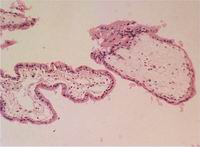

2.部分性葡萄胎:是有大绒毛和小绒毛组成,这些绒毛具有扇贝形(又称海岸形)的特点,伴有滋养细胞包涵体,部分可有轻度的滋养细胞增生。并且可有有胎儿或者胚胎的出现。

部分性葡萄胎里面,看到的滋养细胞增生的相对少,就算有,也是比较轻微,而且面积不大,通常也就囊泡的一角,或者其中部分区域有增生现象。

部分性葡萄胎的囊泡层扇贝形(有些人叫海岸形,波浪形,锯齿形,多角形。。。),外层一般没有,或者少有滋养细胞的增生。并且,多数这种囊泡和完全性的对比能发现,部分性的囊泡周边,有些类似仙人掌那样,上面有些小刺。